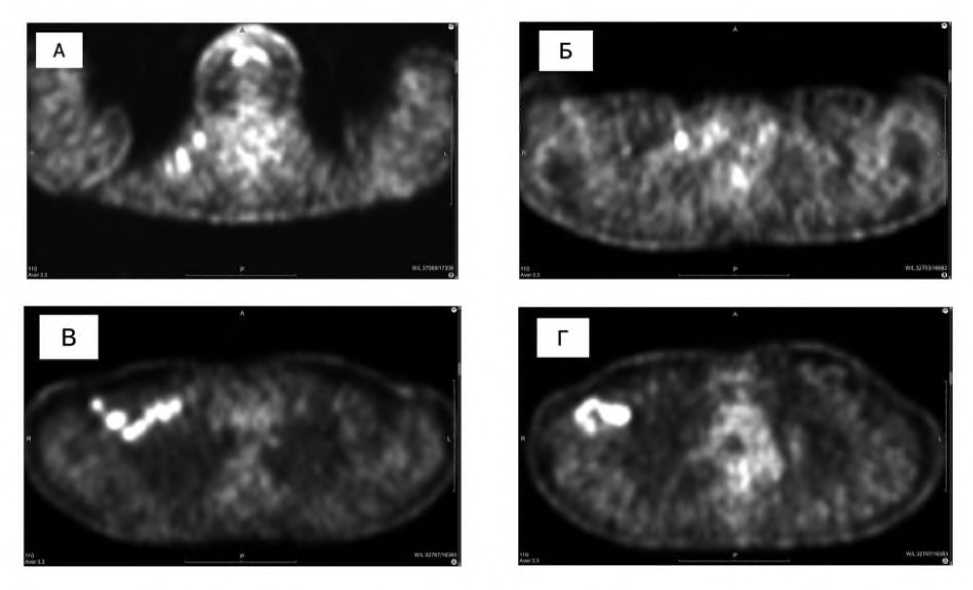

По данным ультразвукового исследования молочных желез (УЗИ) от 05.2024: в верхне-внутреннем квадранте (ВВК) правой молочной железы визуализировалось гипоэхогенное неоднородное образование размерами 18×11 мм с неровными контурами и единичным приводящим сосудом. Ультразвуковое исследование также выявило изменения правых подмышечных л/узлов: обнаружены множественные гипоэхогенные л/узлы с измененным корковым слоем. Л/узлы слева визуализировались, но не были изменены. На шее с обеих сторон выявлены л/узлы: справа — множественные гипоэхогенные от 5 до 9 мм, а слева — одиночные до 7 мм без дифференцировки. Надключичные л/узлы также визуализировались с обеих сторон: справа— множественные округлые до 8 мм с измененным корковым слоем, а слева— единичные размерами 8×3 мм без дифференцировки, при этом подключичные л/узлы не визуализировались. Заключение: по УЗИ признаки образования правой молочной железы, метастатического поражения шейных, надключичных л/узлов с обеих сторон, подмышечных л/узлов справа (Рис. 1).

Рис. 1. УЗИ метастатических аксиллярных лимфоузлов справа от 05.2024. (А) Увеличенный аксиллярный лимфоузел с нарушением дифференцировки. (Б) Увеличенный аксиллярный лимфоузел с утолщенным корковым слоем.